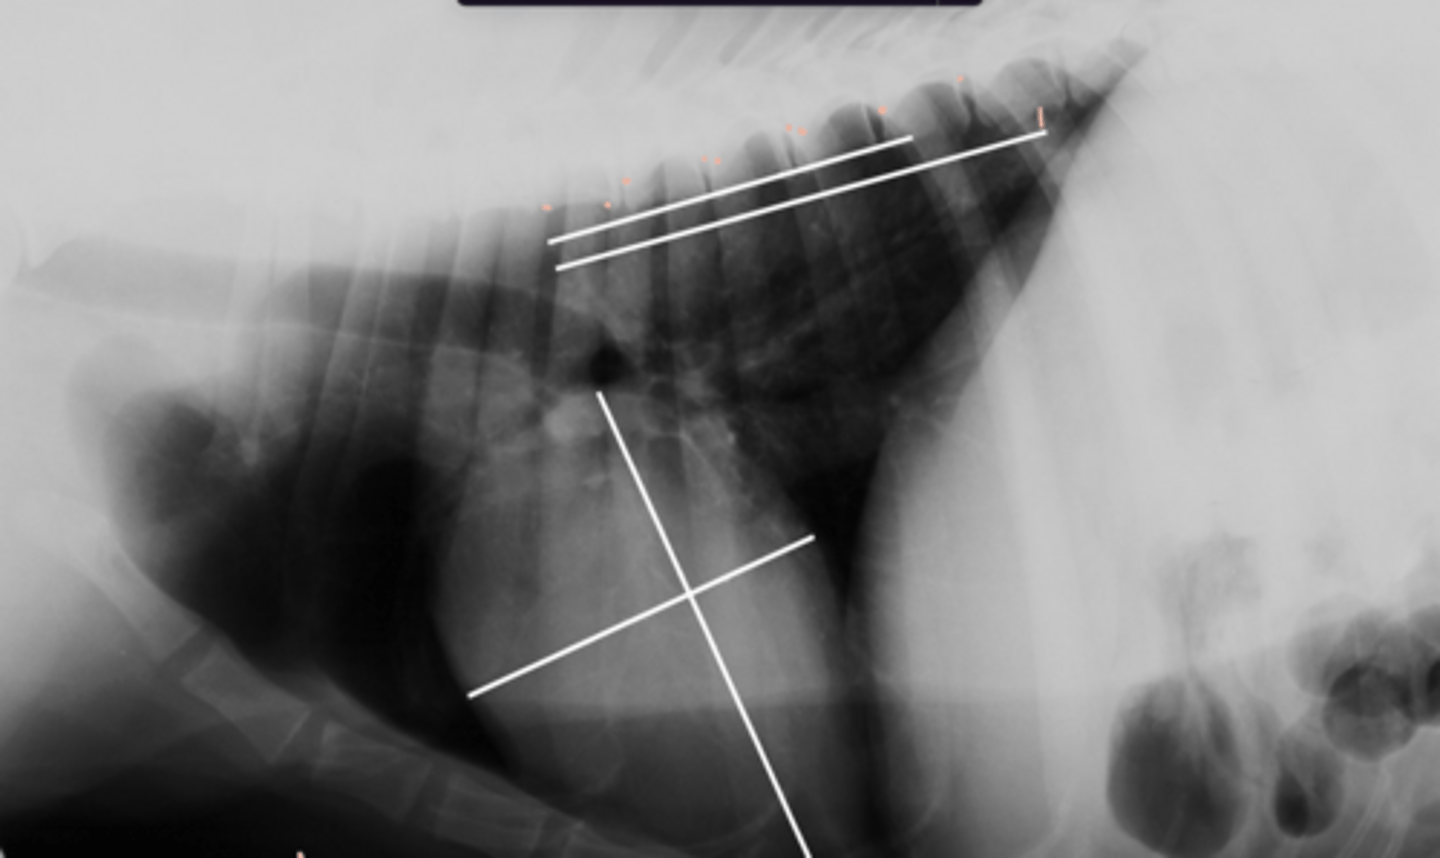

5.7 + 4.3 = 10

(K9 - 10.5)

Given the following radiograph do we have an enlarged heart?

No